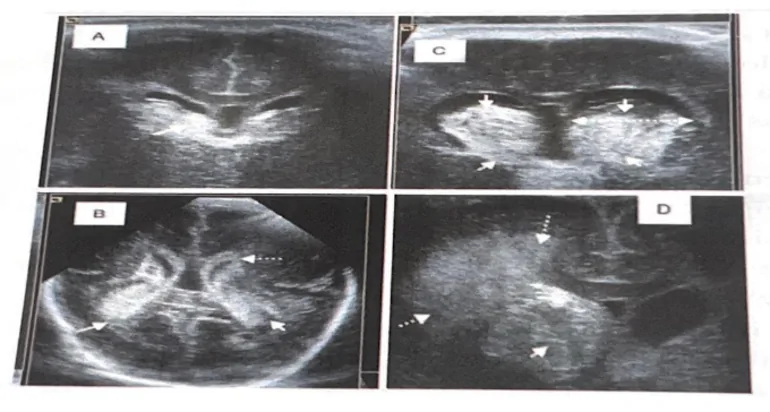

تشمل النزوف داخل القحف التي تحدث لدى المولود ما قبل الأوان نزف المصورة الجرثومية (HMG)، والنزف داخل البُطينات (HIV) والنزوف البرانشيمية، مع كون الأخيرة الأقل تكرارًا. يمكن جمع كل من HMG وHIV تحت مصطلح النزف المحيط بالبطينات – داخل البطينات (HPIV) وهو التعقيد الرئيسي الذي قد يؤدي إلى إصابة دماغية لدى المولود ما قبل الأوان.

المصدر الأكثر شيوعًا للنزوف في دماغ المولود ما قبل الأوان هو المصورة الجرثومية (MG)، وهي بنية تقع في المنطقة تحت البطانة حول البطينات ومزودة بكثافة وعائية عالية. عندما يحدث نزف في MG، قد يتمزق الependimoal الموجود أسفله ويخترق البطينات، مكونًا بذلك النزف داخل البُطينات (HIV) (Ballabh, 2014)

تصنف HPIV في درجات مختلفة تُحدد بوجود أو غياب النزف في البطينات، ونسبة النزف داخل البطينات، ووجود أو غياب احتشاء نزفي محيط البطينات.

- الدرجة I: النزف محصور في MG تحت البطانة،

- الدرجة II: وجود دم داخل البطينات يشغل أقل من 50% من مساحة البطين وبدون توسع بطيني،

- الدرجة III: وجود دم داخل البطينات يشغل أكثر من 50% من مساحة البطين ومع توسع بطيني.

- الدرجة IV: نزف داخل البطينات وبرانشيمي، يتوافق مع احتشاء نزفي وريدي محيط البطينات.

سيؤدي النزف على هذا المستوى إلى فقدان الخلايا السلفية، وبفعل الضغط الناتج عن النزف والإجهاد التأكسدي المترتب عليه ستتفاقم إصابة المادة البيضاء المحيطة، مما يساهم في مَلاَحِقَة المادة البيضاء المحيطة بالبطينات (LPV) (Cerisola et al., 2019.